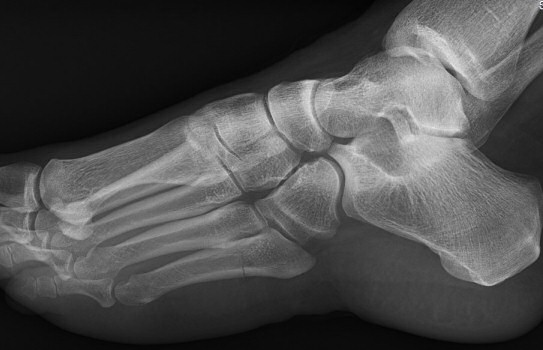

Exempel på Jones-frakturer, första bilden färsk, andra bilden ej läkt, tredje bilden efter operation.